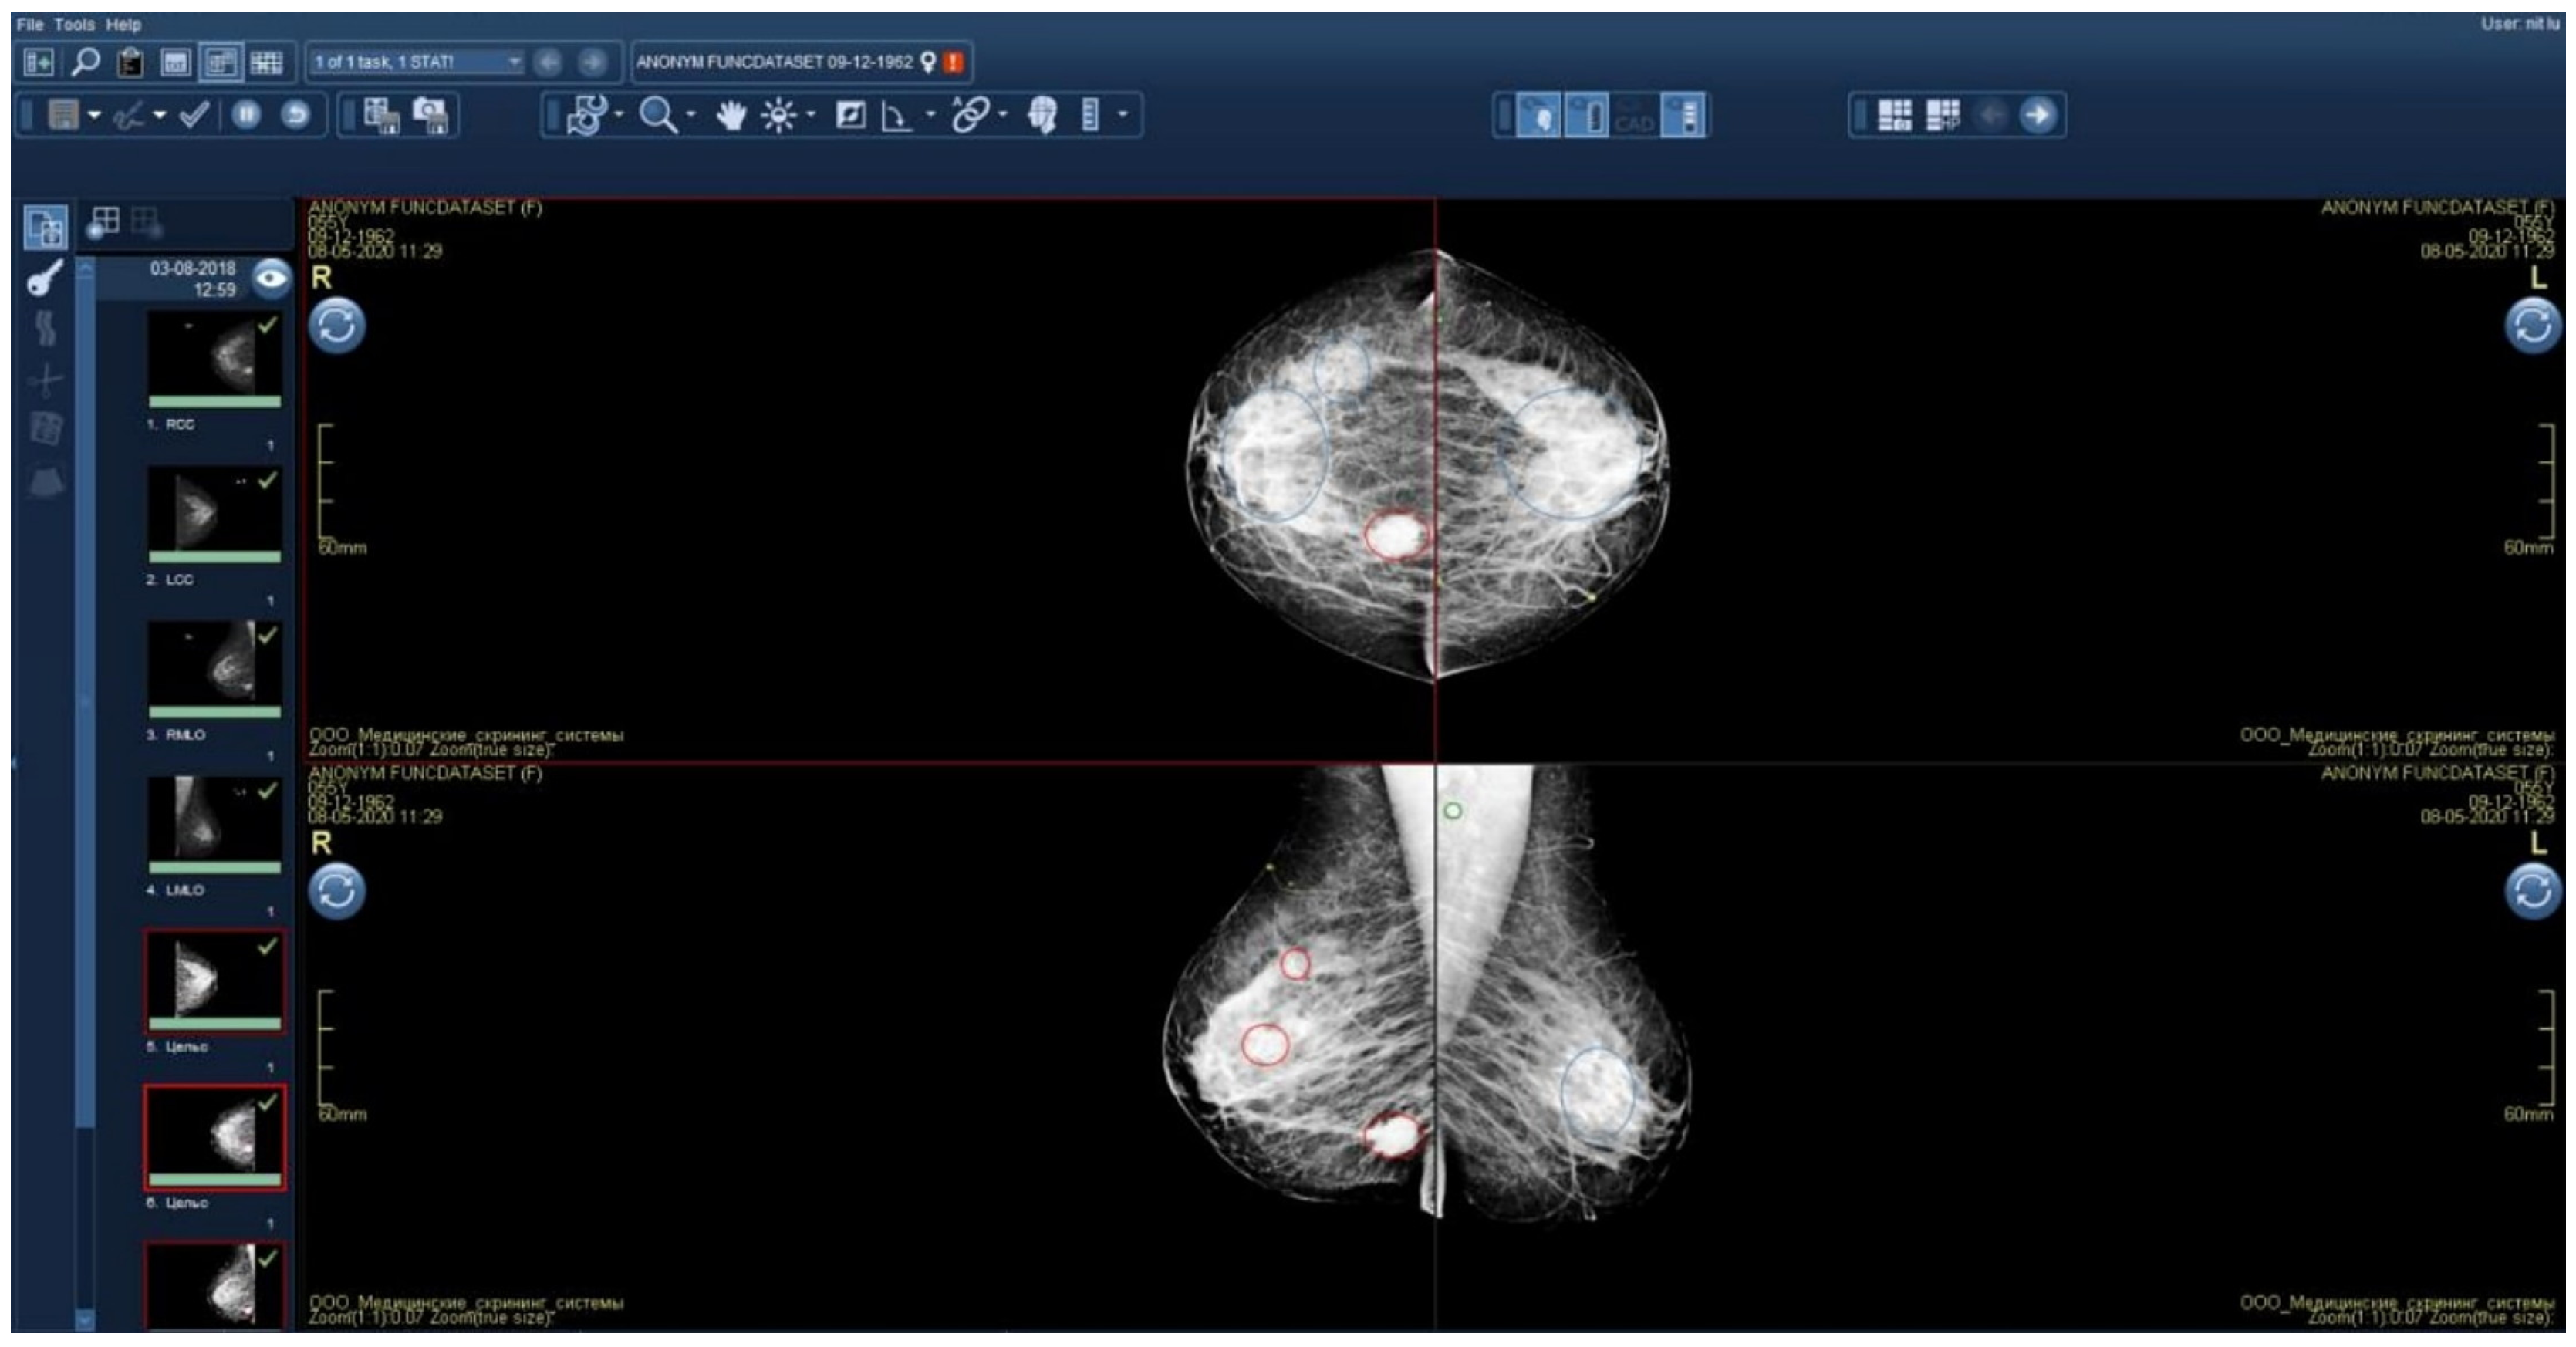

2.5.1. Technical Integration of the AI Solution into the PACS

2.5.2. Functional Testing